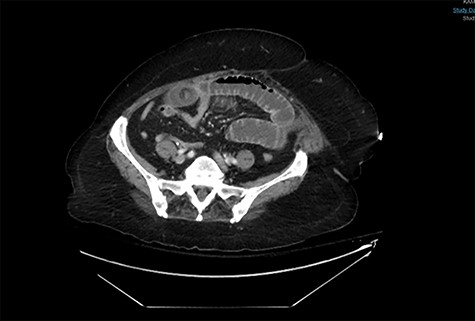

A CT abdomen and pelvis scan showing multiple large stones in the small bowel.

Postoperative course was marked by a slow recovery evidences by persistently high nasogastric tube output and failure to open her bowel. On the third postoperative day, a trial of therapeutic Gastrografin was given, not much improvement was achieved, and the patient continued to be obstructed. A repeat abdominal CT scan was obtained on day 5 due to persistence of intestinal obstruction. It showed dilated contrast-filled small bowel loops with multiple filling defects, indicating recurrent GSI (Fig. 4).